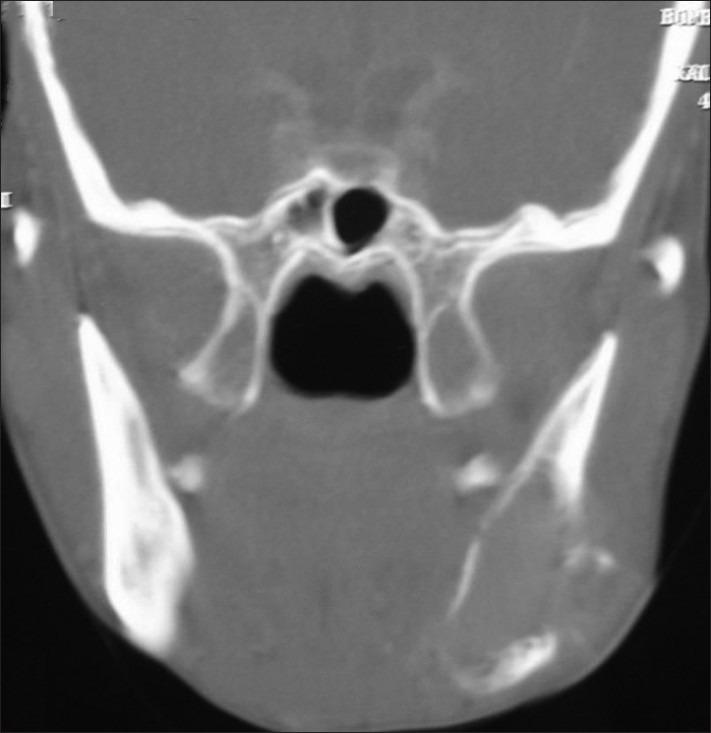

Mandibular metastasis due to thyroid carcinoma is not very frequent and the cases described in the literature are few. Due to its bloodstream dissemination, most of them are a consequence of the follicular variant of thyroid carcinomas. We are presenting a case in which the metastatic lesion of mandible was detected before diagnosis of primary malignancy.